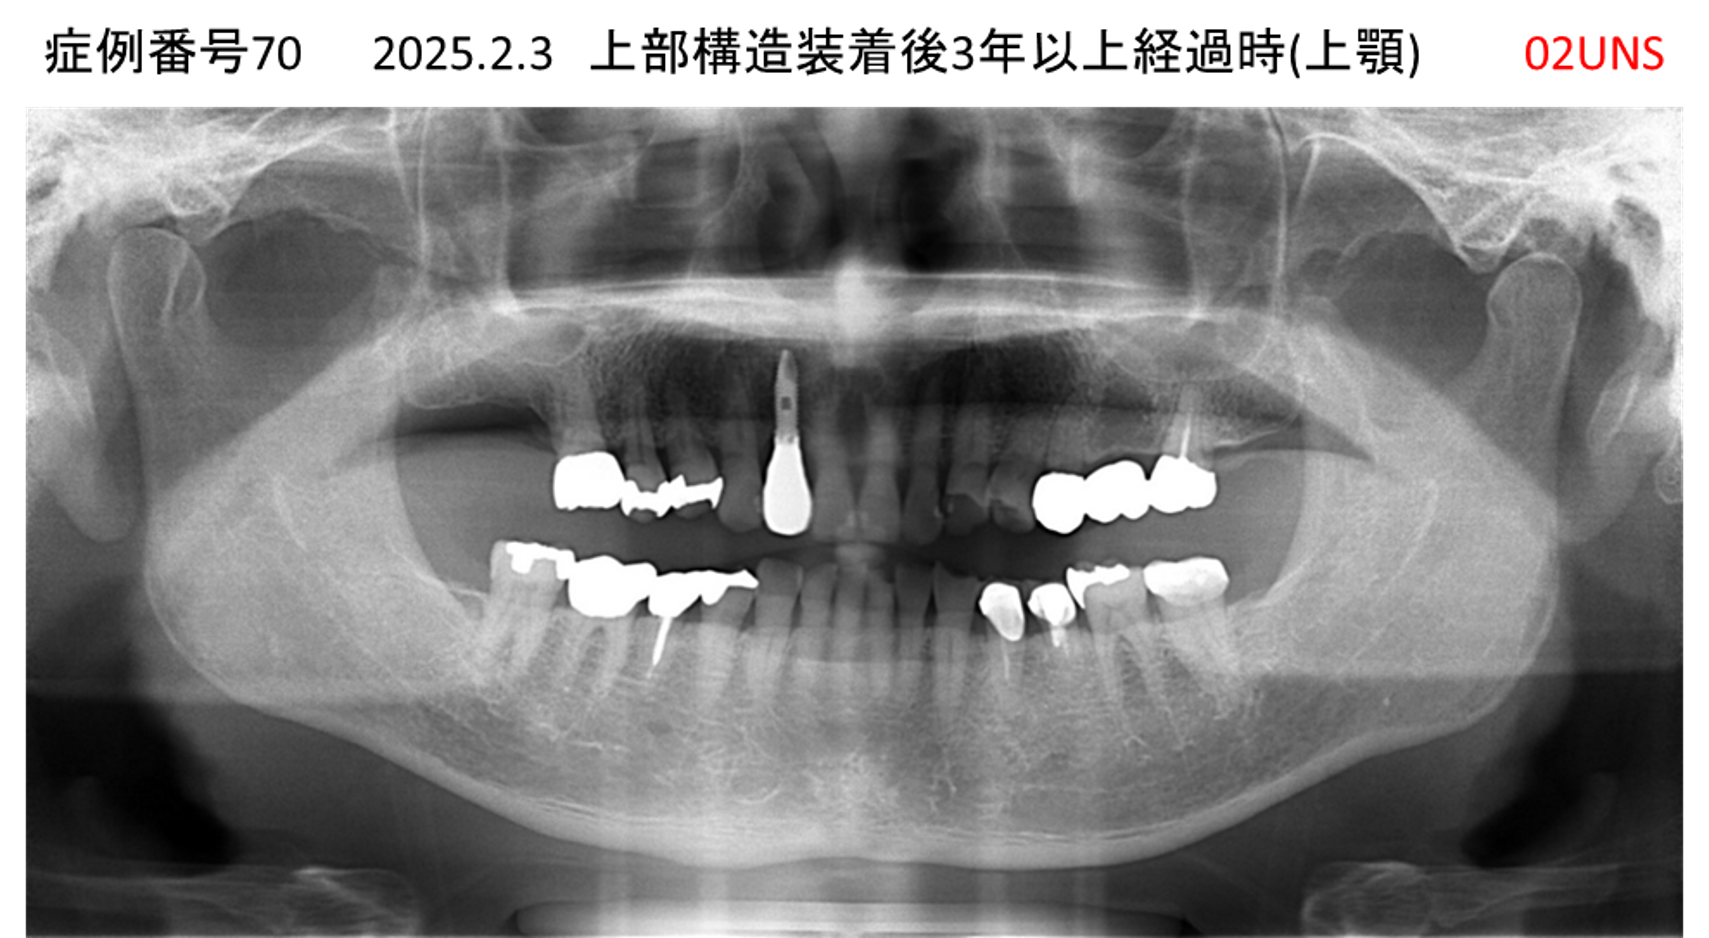

上の前歯が揺れてきてかめない患者様のインプラント症例

| 治療名称 |

インプラント |

| 治療費用 |

440万円+税 |

| 治療期間 |

6か月 |

| 患者さんの症状(主訴) |

上の前歯が揺れてきた。かめない |

| 治療内容 |

サイナスリフト、GBR、インプラント、即時荷重 |

| 治療結果 |

上の前歯の揺れが収まった。奥歯でしっかり噛める。 |

| 治療の注意点(リスク/副作用) |

インプラントが壊れたら再治療が必要 |